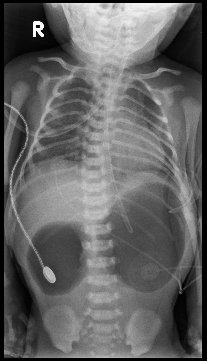

【113-1 醫學(五) 第46題】

一位 6 個月大的幼兒過去無任何病史,因頸部胸鎖乳突肌前緣皮膚有一小開口且有分泌物(如圖所示)接受手術,最可能的診斷為何?

破題關鍵

這道題目的解題核心在於辨識頸部病灶的「位置」與「型態」。圖片中顯示在幼兒頸部外側、胸鎖乳突肌前緣有一個小開口並有分泌物,這正是第二對鰓裂遺跡瘻管的典型表現。